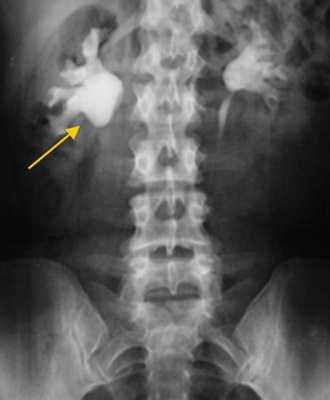

Рентгенологические методы обследования

Если нет противопоказаний, то рентгенологические исследования с контрастом являются приоритетными в диагностике гидронефроза.

Экскреторная урограмма. Стеноз лоаночно-мочеточникового сегмента, гидронефроз справа.

Благодаря рентгеноконтрастным препаратам метод дает оценку экскреторным функциям почек. Он эффективен на начальных стадиях заболевания, по мере нарастания патологии диагностическая эффективность снижается.